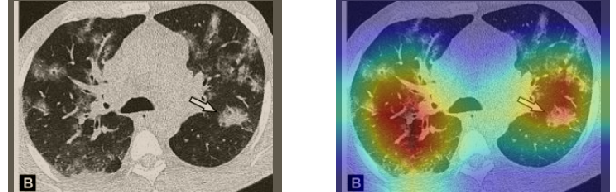

In order to make our models more transparent and provide detailed visual analysis, we present the Grad-CAM localization maps obtained by different models. We consider CT images with COVID-19 abnormalities from the test set of each dataset and highlight the important regions considered for the prediction. For the SARS-CoV-2 dataset we use the Inception V3 model. Figure 13 shows the original CT images and their localization maps. Our model is capable to detect regions that show abnormalities in the CT scans.

In a similar way, we consider classifying the test CT scans from the COVID-19 dataset by the DenseNet169 model and highlight the important regions considered for predictions. We present the original CT images and their localization maps in Figure 13. We can also see that our model is capable to detect the COVID-19 related regions as marked (small square in some images) by expert radiologists.

A wide variety of typical and atypical CT abnormalities have been reported for COVID-19 patients in various studies [58, 59]. So, we tested our models on external CT images extracted from these two publications as they feature typical findings of COVID-19 pneumonia marked by specialists. In order to make sure that not any of the extracted images are unintentionally included in our datasets, specifically the COVID19-CT dataset, we use the model trained on the SARS-CoV-2 dataset. First, the InceptionV3 model is employed to classify the extracted CT images. The model is able to correctly classify the given CT images as COVID-19. Second, in order to interpret the model’s generalization capabilities, we apply the Grad-CAM technique to visualize the regions of abnormalities that are considered. By assessing the different CT images in Figure 15, we can see that the model accurately localizes the disease-related regions. Even more interesting is the fact that the model ignores any specific marks in the images like letters and only localizes the COVID-19 related regions. These visual explanations show the success of our models to learn relevant, generic visual features related to COVID-19 and are capable to correctly classify CT images outside the datasets on which they are trained.